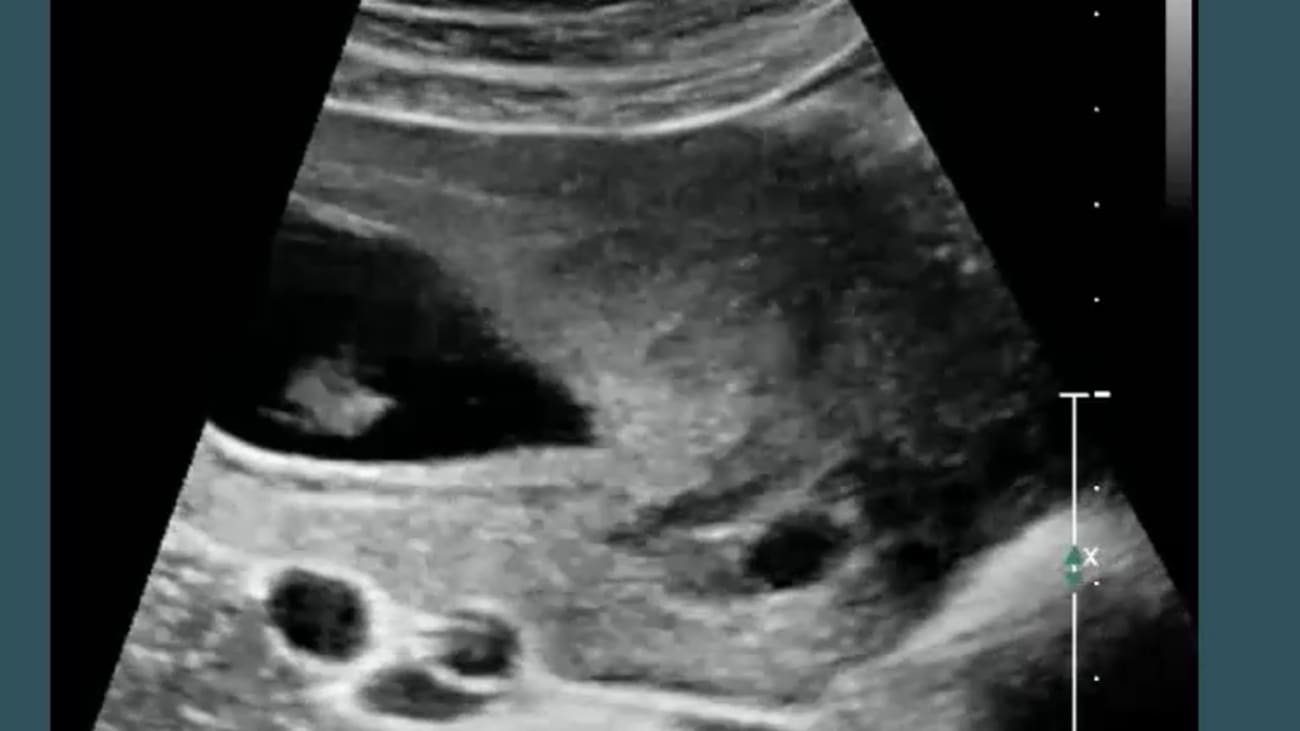

Robert Harris, MD, MPH, FACR, reviews normal findings and landmarks in a first trimester ultrasound. He talks about some abnormal intrauterine findings and indications for first trimester ultrasounds.